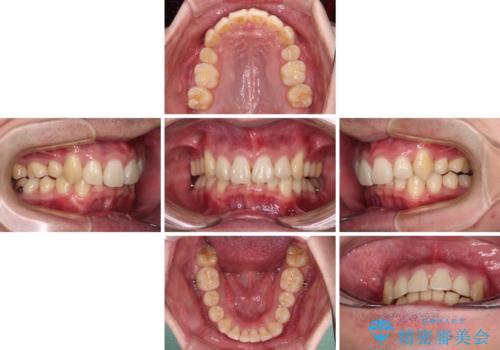

- 八重歯を気にして来院された患者様です。

顕著な上顎の八重歯とディープバイトであったため、上顎の左右第一小臼歯を抜歯することとしました。

犬歯歯根の位置や奥歯の咬み合わせから、ワイヤー装置での治療を強くおすすめいたしましたが、ご本人の強い希望により、妥協的な仕上がりとなることを了解いただき、インビザラインにて矯正治療を行うこととしました。

インビザライン単体で、左右ともに移動の難しい位置に歯根のある犬歯を整えるのは困難と判断し、補助装置を併用することとしました。

ディープバイトや奥歯の咬み合わせなど、インビザライン矯正では限界がありワイヤー装置での治療に及ばない仕上がりとなりました。

ただし、患者様としては八重歯や、それに伴う唇の閉じにくさが改善されたとのことで、納得いく状態での治療終了となりました。